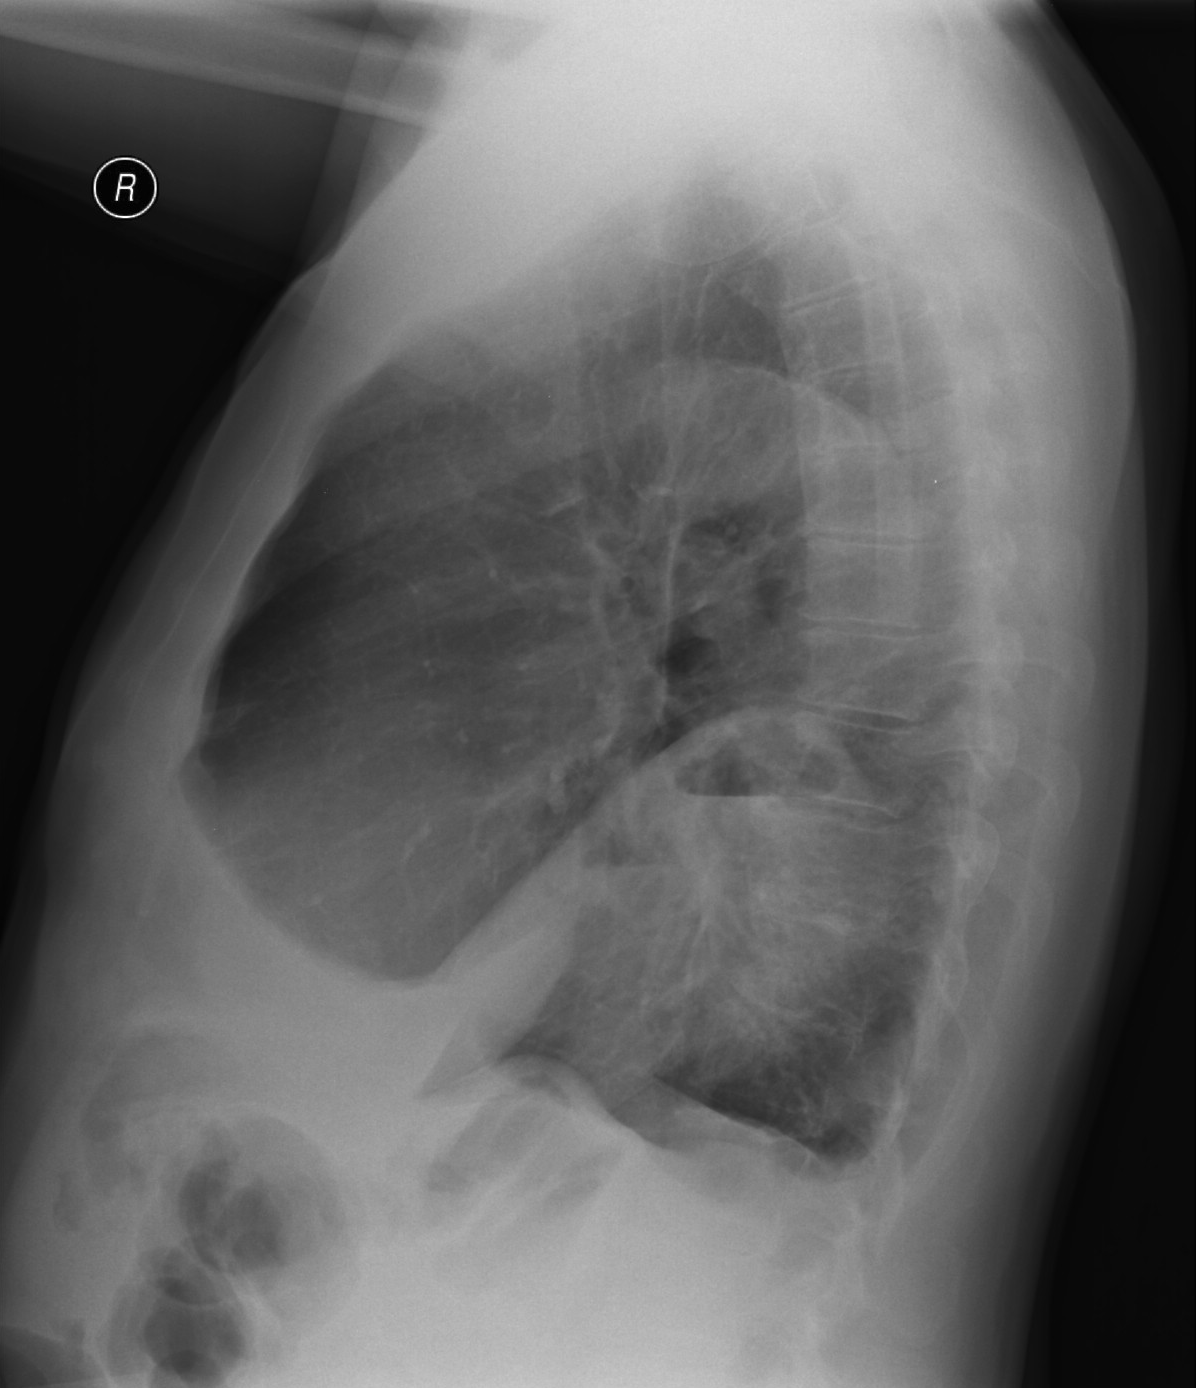

5a,b: Lung abscess. Chest radiograph, bidirectional (PA+lateral - right side near the film).

61 year old woman. Laparoscopic esophagus diverticulum resection 2 months ago. 7 cm air-fluid level with air space above: „basket sign” above the right diaphragm laterally measuring 2,5 cm in lateral diameter and 7 cm mediodorsally.